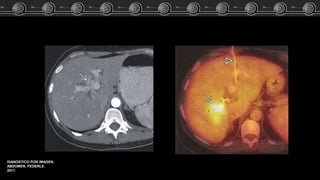

Adenoma, Hemangioma óHNF?? Caso Clínico Fem de 83 años…. El estudio TC demostró lesión focal a nivel del lóbulo izquierdo del higado. ARCHIVO DOCENTE DE TOMOGRAFÍA Y RESONANCIA C.M.C.